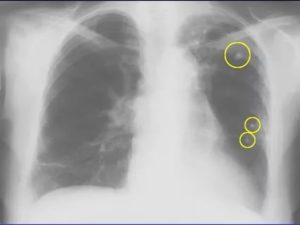

При пневмонии видны множественные (не единичные, по крайней мере) инфильтраты в нижних долях легких – чаще всего только с одной стороны, справа.

При туберкулезе же процесс обычно двухсторонний, плотные очаги могут располагаться как в нижней, так и в верхней части лёгких.

Четкость границы очага позволяет исключить онкологию: дело в том, что контур раковой опухоли обычно нечеткий, «лучистый», несимметричный и изменчивый.

При воспалении легких фиксируются множественные инфильтраты в нижних долях органа, как правило, с правой стороны. В отличие от пневмонии, туберкулез характеризуется плотными очагами, расположенными в любой части легкого.

Поражения легочной такни при туберкулезе на снимках видны более отчетливо и имеют визуальные очаги деструкции и диссеминации легочной ткани.

При наличии такого заболевания, как пневмония, на снимках видны множественные уплотнения в нижних сегментах лёгкого. Опытный и квалифицированный врач сможет отличить образования от раковых. Атипичные опухоли характеризуются нечётким контуром и несимметричным.